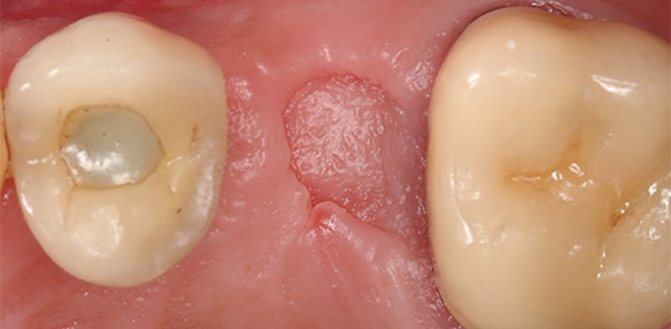

Образование дефекта гайморовой пазухи – это осложнение при проведении манипуляций на верхней челюсти. Образуется отверстие между полостью рта и основной пазухой. Это может произойти при удалении коренных зубов верхней челюсти (моляров и премоляров) или при протезировании. А также при сложном эндодонтическом лечении корня зуба и удалении кистозных образований. Дефект формируется в месте лунки зуба.

Если стенку гайморовой полости повредили при проведении имплантации или другой стоматологической процедуры, врач это заметит. Инструмент примет нехарактерное положение в лунке и будет проваливаться глубже, чем необходимо.

- Тщательно осмотреть зубную лунку, после того как удалили корень зуба.

При несвоевременном обнаружении и ликвидации дефекта острое воспаление утихнет. В течение месяца у пациента образуется свищ. Он соединяет поверхность десны и полость пазухи. Присоединяются признаки хронического воспалительного процесса. Это будет являться тяжелым осложнением.

Гайморит – воспаление слизистой оболочки пазухи. Как правило, развивается после проникновения патогенных микроорганизмов из одонтогенных очагов инфекции.Возникновение свищевых ходов, идущих от пазухи к слизистой оболочки в области удаленного зуба.